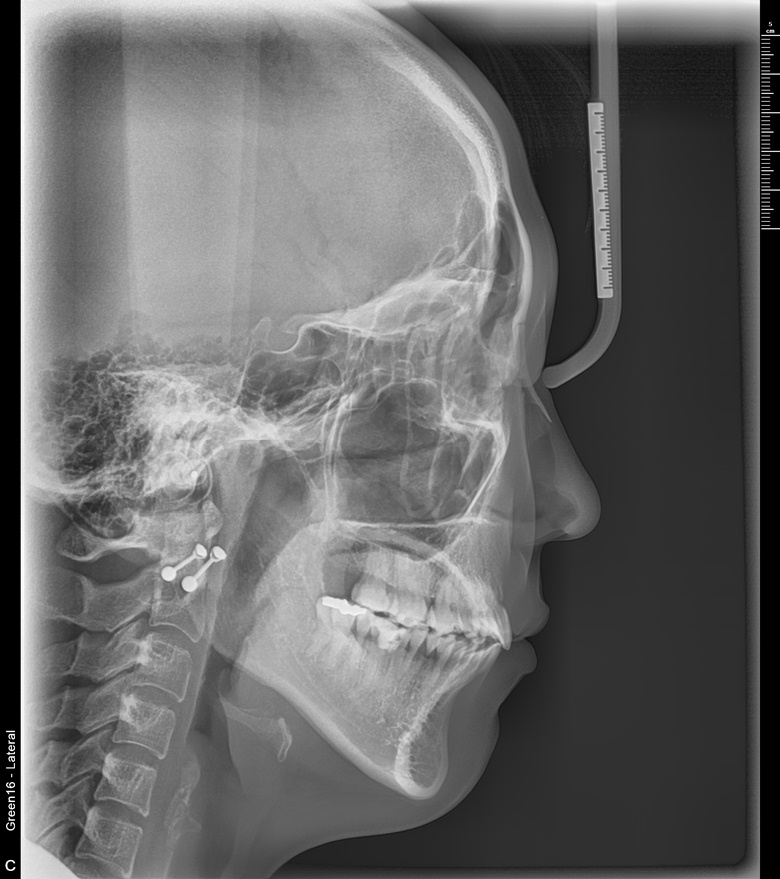

치료 후 사진입니다.